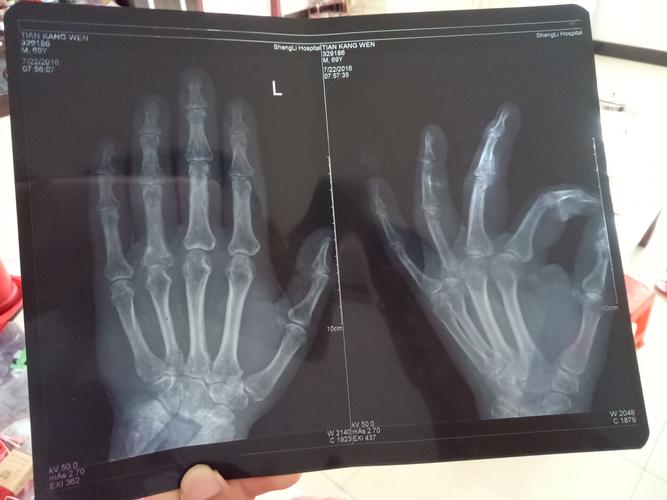

手指骨折x光图片报告

手指骨折x光图片报告,手腕骨折检查报告图片

左手无名指近节指骨基底部横行骨折复查,正位,断端对位对线良好

这个x光片看来拇指有脱臼或者骨折吗